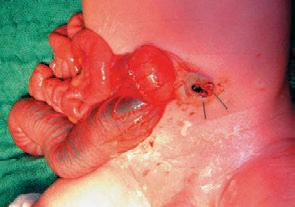

gastrointestinální systém nekrotizující enterokolitida (NEC)

Typické komplikace RDS jsou pulmonální intersticiální emfyzém, pneumotorax, pneumomediastinum, pneumoperitoneum, pneumoperikard, bronchopulmonální dysplazie, perzistující ductus arteriosus, perzistující fetální cirkulace (syndrom PFC), nekrotizující enterokolitida, rovněž může vzniknout i krvácení do mozku.

n Léčba

Symptomatická léčba spočívá v podání kyslíku a umělé plicní ventilaci, v infuzní terapii u oběhové nestability a velmi důležitá je šetrná manipulace s dítětem!

Kauzální léčba představuje podání surfaktantu vepřového nebo hovězího (v České republice se používá Curosurf® suspenze – phospholipida pulmo-

Obr. 1.5a Syndrom dechové tísně u předčasně narozeného novorozence, RTG snímek hrudníku po intubaci, který byl provedený za 2 hodiny po porodu: mléčná snížená transparence, vzdušný bronchogram, kontury srdeční a mediastina neostré

nis suis 80 mg v 1 ml suspenze, Chiesi Farmaceutici

S.p.A., Parma, Itálie; držitel registračního rozhodnutí – poznámka překladatele). Po podání surfaktantu dojde ke zlepšení oxygenace a ke zlepšení výměny krevních plynů, snižuje se incidence pneumotoraxu a sníží se i mortalita, která je spojena s RDS a vznikem bronchopulmonální dysplazie.

Indukce plicní zralosti: těhotným se podává 48 hodin před porodem betametazon, který indukuje syntézu surfaktantu ještě před porodem. K tomu je nutné připomenout i význam šetrně vedeného porodu a optimálně prováděné primární resuscitace těchto rizikových dětí.